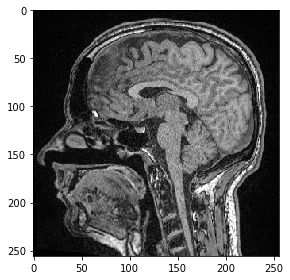

Corte#

Para visualizar imágenes 3D usando imshow de scikit-image, necesitamos seleccionar un corte para visualizar. Por ejemplo, un corte en Z:

slice_image = image[100]

imshow(slice_image)

<matplotlib.image.AxesImage at 0x2b54f73d340>

../_images/b9ec53895c9942461dd35e1b88b95a9557441ceb09c074bd865d8bb6ddfdb74b.png